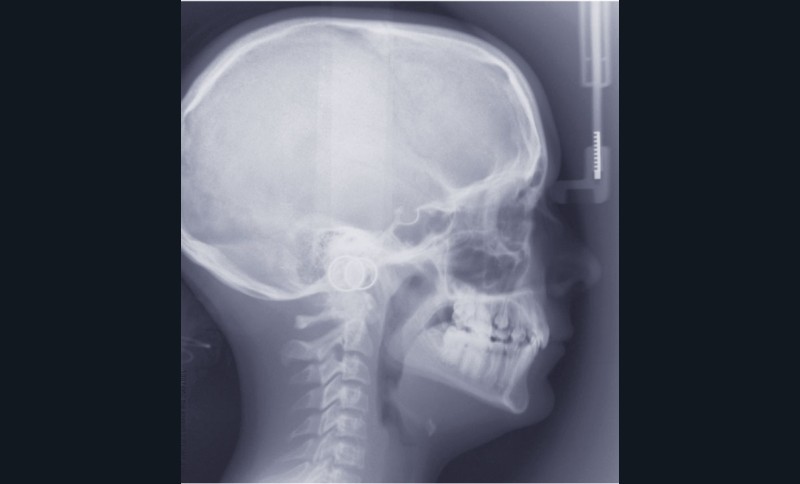

Ludivine T. âgée de 12 ans et demi présente une agénésie des deux incisives latérales maxillaires dans un contexte occlusal de classe II division 2 (fig. 1 à 3).

L’examen clinique exo-buccal révèle un visage équilibré en classe I squelettique tendance hypodivergente. De profil, le menton est marqué et le profil sous nasal très légèrement concave (fig. 1).

Le contexte de classe II occlusale, l’évolution spontanée mésiale des 13 et 23 et le diamètre mésio-distal favorable des canines conduisent au choix d’une thérapeutique par fermeture orthodontique des espaces d’agénésie avec substitution de 13 et 23 en place de 12 et 22. Le traitement de l’arcade mandibulaire ne nécessitant pas d’extraction, l’occlusion de fin de traitement sera donc une classe II molaire thérapeutique.

La difficulté du traitement réside dans la correction de la supraclusion incisive et surtout le contrôle de l’inclinaison des incisives maxillaires pour assurer un soutien suffisant des lèvres et limiter les risques de récidive.